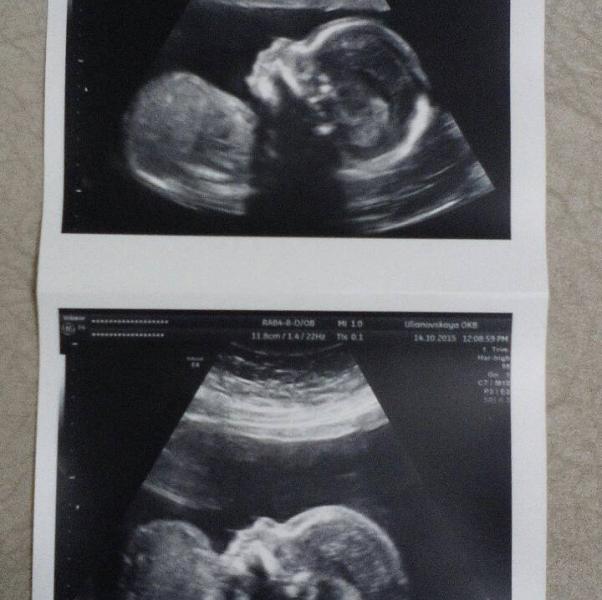

Давайте покидаем фото с УЗИ наших малышей)))) посмотрим и порадуемся за наших детишек))) Пусть растут здоровенькими)) Вот мой малышок)) в 20 недель)

@eeeeevgeny, да, я тоже через недельку опять на УЗИ и новые фото сделаю))) готова каждую фоточку в рамочку и по всей квартире)))